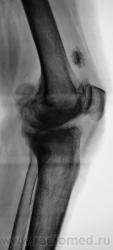

Пациентка направлена на рентгенографию коленного сустава с диагнозом "Деформирующий артроз".

Выраженный деформирующий артроз, множественные хонтроматозные тела в полости сустава.